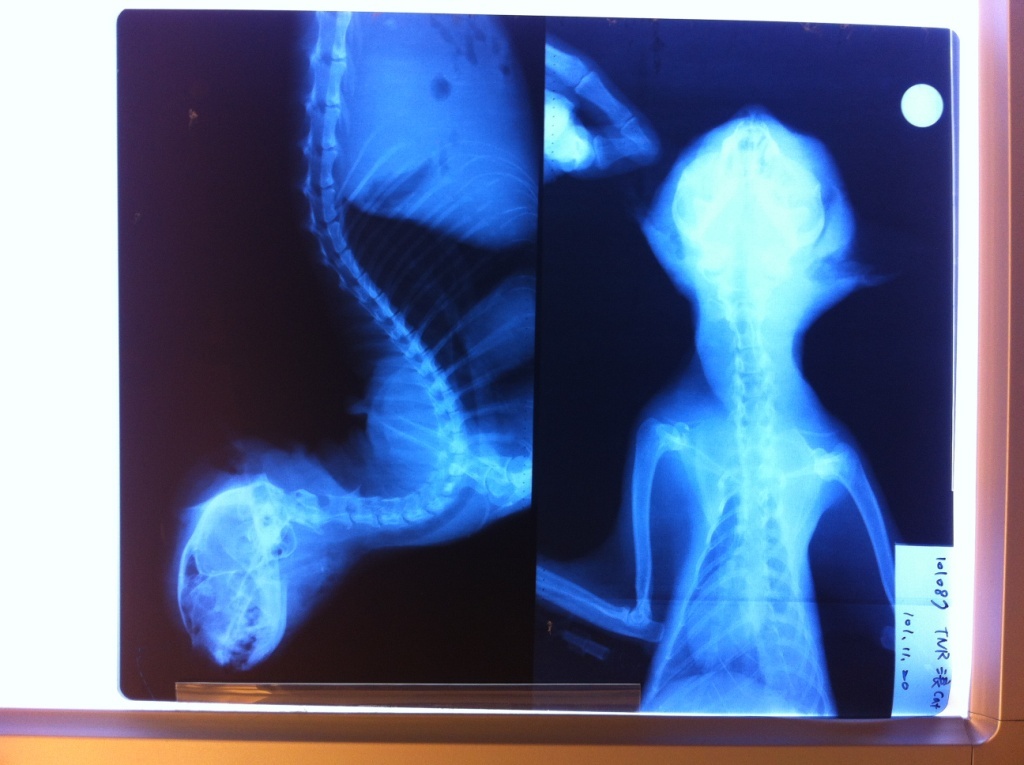

主題: 中壢環中東路被狗咬傷黑貓 申請者姓名: 林 ミドリ 花色: 申請日期: 2012-11-28 12:23:16 申請者部落格: 申請者臉書網址: 所在縣市/合作醫院: 桃園縣/思邁爾動物醫院 治療費用: 13500元 需求人數: 14人 已結案 (2013-02-23 14:44:48) 報名人員: Hill Lin(已付款)、Niko Lin(已付款)、Hui Mei Chen(已付款)、Alumi Lu(已付款)、楊舒琇(已付款)、Ya-Hsien Yang(已付款)、Norman Wu(已付款)、Justin Wang(已付款)、Alley Wang(已付款)、喵喵(已付款)、陳品璇(已付款)、tzuying(已付款)、洪劍睿(已付款)、Maureen Chang(已付款)、 候補人員: 薇薇真、 動物病情說明: 11/19中午朋友在環中東路發現"老黑"蹲在路邊,徬晚發現"老黑"仍在原地,朋友來電詢求支援,詢問協會後送到中壢思邁爾醫院,"老黑"右半臉有撕裂傷,傷可見骨,身上也有多處傷口

11/20朋友至醫院觀看"老黑",醫生告知"老黑"傷勢嚴重,除了身上傷口之外,失溫脫水,腹部有積水,無法抽出腹水檢驗,無法自己進食,可能要考慮安樂死

11/21醫院通知脫水狀況已經康復,腹部積水也排除是腹膜炎所造成的,可以自己進食,會安排清創手術

11/22下午三點進行清創手術,手術的過程,大致上順利,這三天是"老黑"的關鍵觀察期,因為手術前醫生發現"老黑"的舌頭已經有壞死的跡象產生,這種狀況有可能是因為傷勢拖得太久所以引起的敗血症,可是目前的血液報告卻沒有敗血症的跡象,所以這幾天會持續抗生素的治療,看看這三天的白血球指數是否會降下至標準左右。

11/23下午接到朋友電話告知,醫院通知"老黑"發生休克情形,經搶救後仍不治死亡